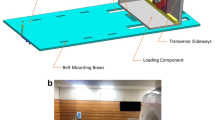

A 13-channel RF receive array was constructed, and the crucial choice of the array element size (based on considerations like region of interest, geometry of the minipig’s knee, achievable signal-to-noise ratio, applicability of parallel imaging, etc.) was determined using the Q factors of loops with different sizes. A special movement device was constructed to guide and produce a reproducible motion of the minipig’s knee during acquisition.

The constructed array was electrically characterised and the reproducibility of the cyclic motion was validated. Snapshots of dynamic in vivo images taken at a temporal resolution (308 ms) are presented. Some of the fine internal structures within the minipig’s knee, like cruciate ligaments, are traced in the snapshots.